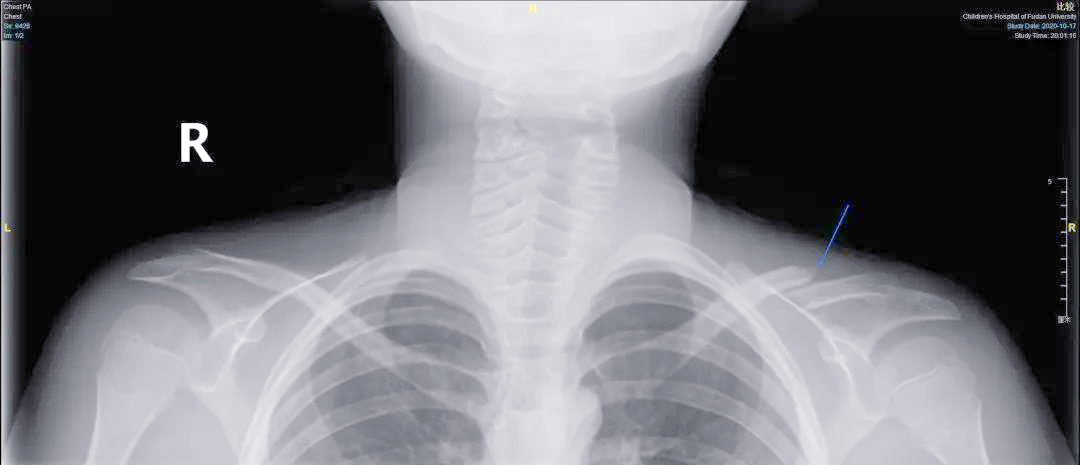

儿童的锁骨骨折很常见,绝大部分无需手术#锁骨骨折#儿童骨科

微创技术助力青少年锁骨骨折治疗